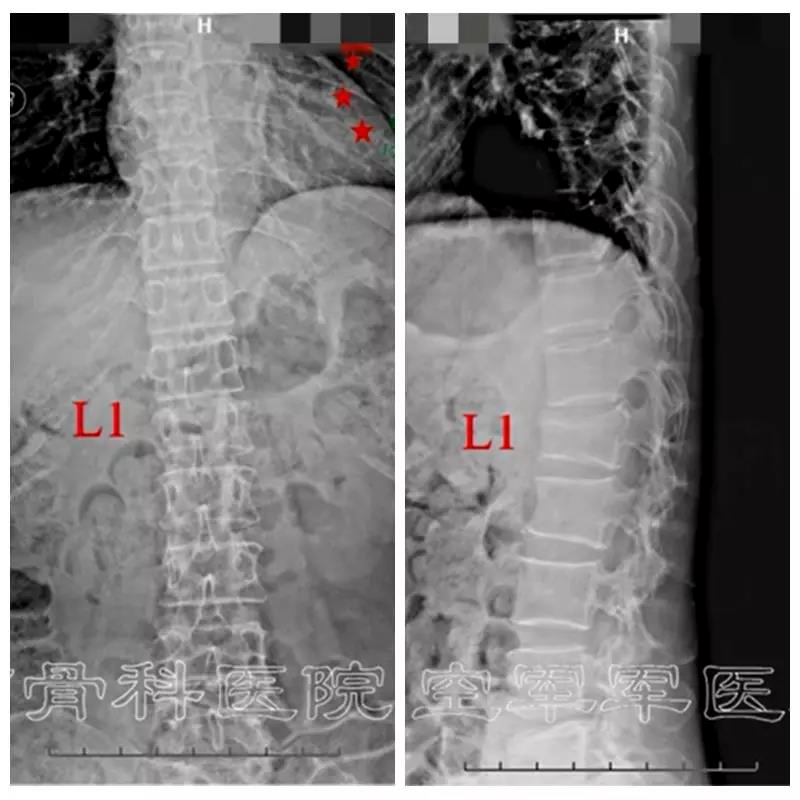

术前X线正侧位片